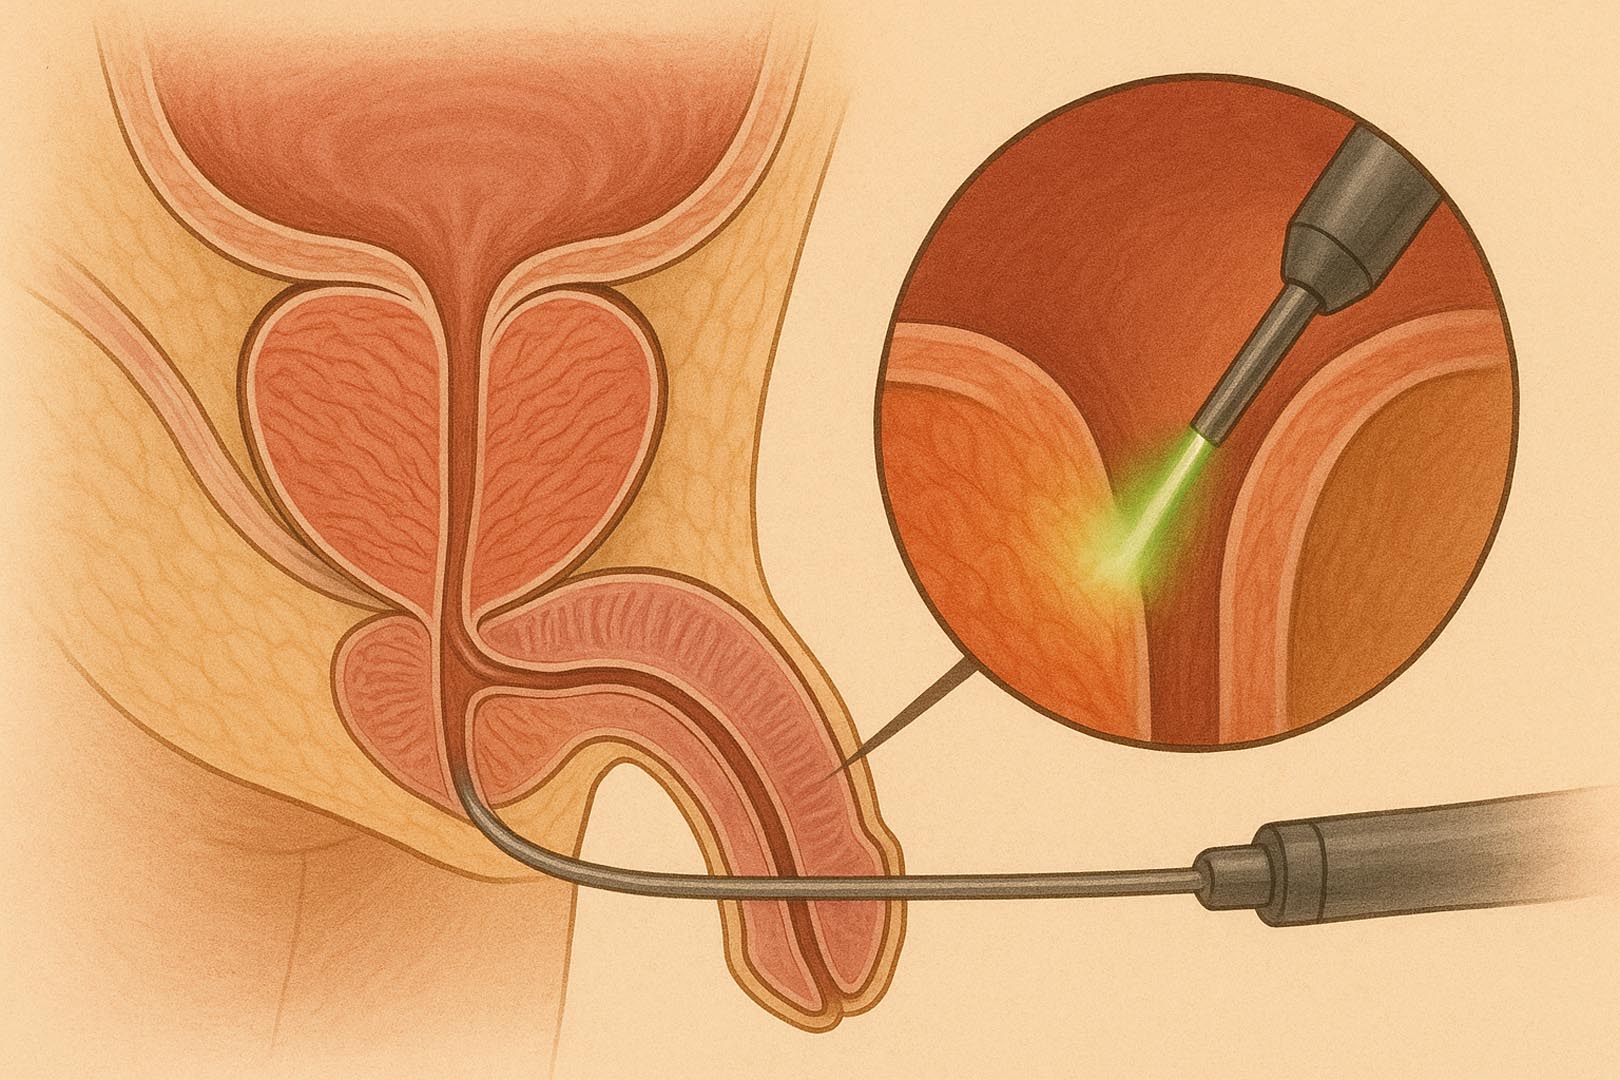

Green Laser - Vaporizzazione Fotoselettiva della Prostata

Tecnica endoscopica laser con vaporizzazione precisa. Ideale per prostata fino a 80-100 cc. Efficace nel ripristinare il flusso urinario. Minimo rischio emorragico, anche in pazienti anticoagulati.